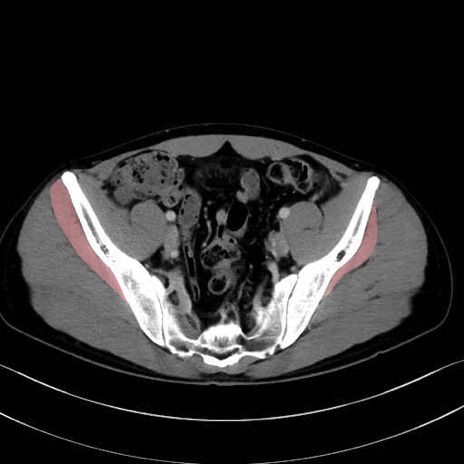

小殿筋 (Gluteus minimus)